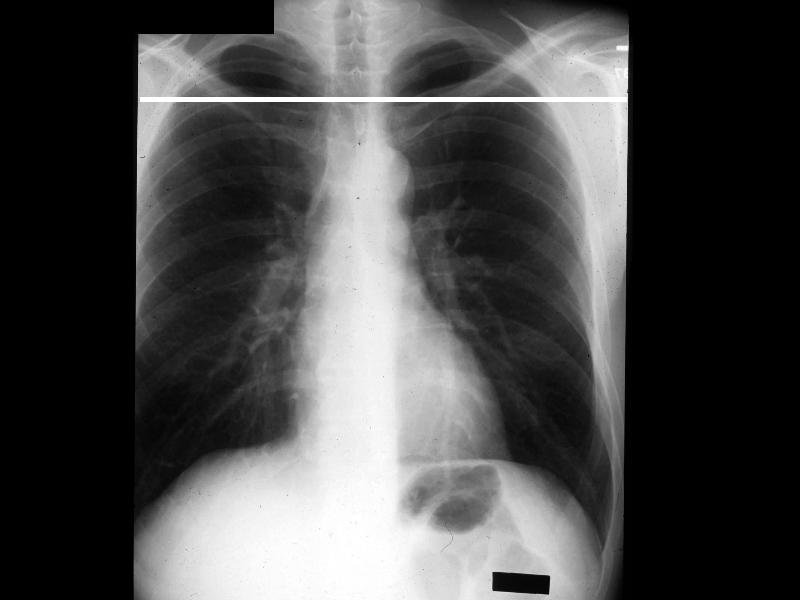

MS 202 CXR NL PA